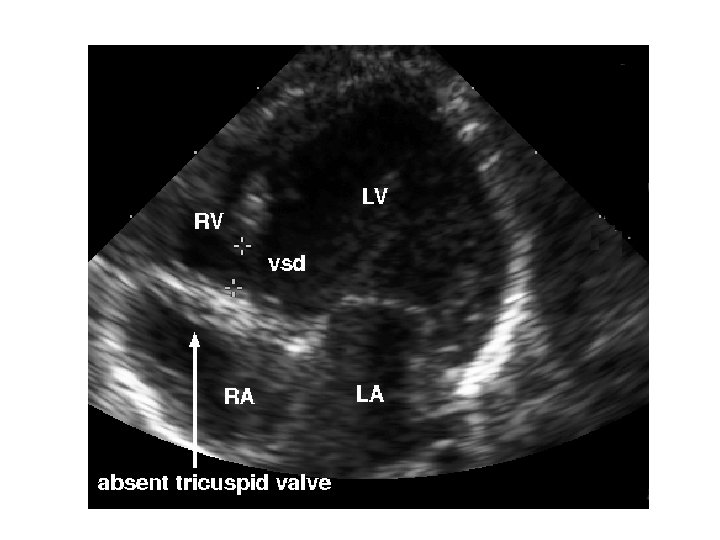

The target diagnosis • Critical congenital heart disease (CCHD) • CHD which is duct dependant and may cause sudden severe illness after PDA closure, and CHD which requires surgery in the 1 st 28 days of life • Includes most cyanotic CHD, and left heart obstructive lesions

False negatives • 17% of infants with CCHD which was not diagnosed antenatally will still be discharged without diagnosis • Mostly Coarctations, IAA occasionally others (TGA…) • Must be sure that parents know (just as with other screens) that a negative screen is not 100%, and babies still need normal health care